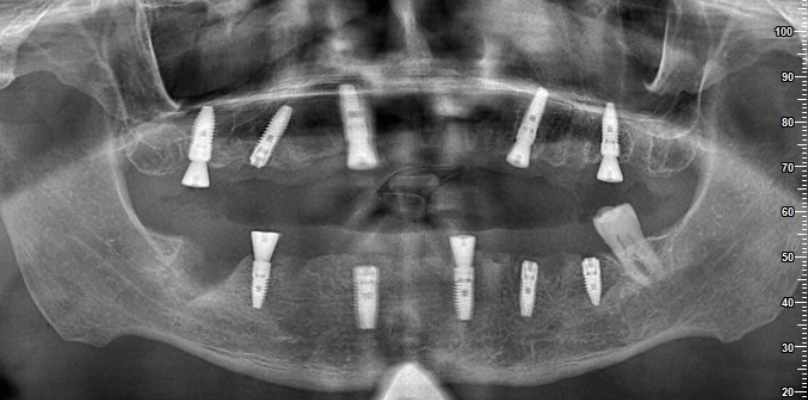

Dans les étapes ultérieures, vous pouvez regarder des vidéos sur la façon de placer des implants et de produire des prothèses. Ces vidéos visent à fournir une perspective informative à nos patients en montrant chaque étape du processus. Chaque étape est réalisée minutieusement par nos médecins experts.